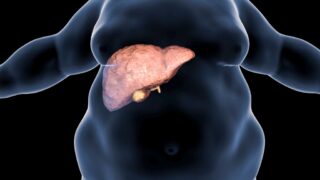

ダイエットコラム 脂肪肝が肝臓に及ぼす驚くべきダメージ!?ダイエットで改善する方法とは?

脂肪肝は甘いものや揚げ物、アルコールの過剰摂取、不規則な生活習慣などが原因で起こる。適切なカロリー摂取量の設定や健康的な食生活、運動、アルコールの控えなどで改善可能。医師や栄養士のアドバイスも重要。肝臓は体内で重要な役割を果たすため、脂肪肝の改善は健康にとって重要。